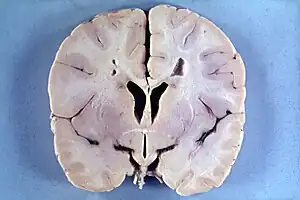

Many people with abnormally large heads or large skulls are healthy, but macrocephaly may be pathological. Pathologic macrocephaly may be due to megalencephaly (enlarged brain), hydrocephalus (abnormally increased cerebrospinal fluid), cranial hyperostosis (bone overgrowth), and other conditions. Pathologic macrocephaly is called "syndromic", when it is associated with any other noteworthy condition, and "nonsyndromic" otherwise. Pathologic macrocephaly may be caused by congenital anatomic abnormalities, genetic conditions, or by environmental events.[3]

Megalencephaly and hemimegalencephaly

Diagnosis

Macrocephaly is customarily diagnosed if head circumference is greater than two standard deviations (SDs) above the mean.[11] Relative macrocephaly occurs if the measure is less than two SDs above the mean, but is disproportionately above that when ethnicity and stature are considered. Diagnosis can be determined in utero or can be determined within 18–24 months after birth in some cases where head circumference tends to stabilize in infants.[12] Diagnosis in infants includes measuring the circumference of the child's head and comparing how significant it falls above the 97.5 percentile of children similar to their demographic. If falling above the 97.5th percentile then the patient will be checked to determine whether there is any intracranial pressure present and whether or not immediate surgery is needed.[2] If immediate surgery is not needed then further testing will be done to determine whether the patient has either macrocephaly or benign macrocephaly.